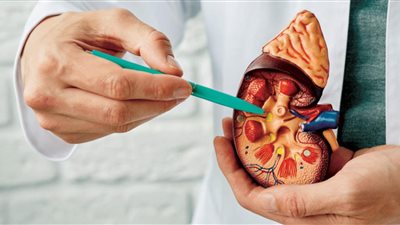

استشاري يكشف 4 مراحل للإصابة بسرطان الكلى.. وهذه أبرز الأعراض

يعتبر سرطان الكلى من ضمن أنواع السرطانات التي تصيب في الغالب الرجال عن النساء، وخاصة في سن من 50 لـ 70 عاما، حيث يتم تصنيف سرطان الكلى وفقًا لمدى تقدم السرطان ومدى انتشاره في الجسم.

ويمر سرطان الكلى بـ 4 مراحل، حيث يستعرض موقع «صحة 24»، التفاصيل الكاملة حول هذا الأمر، وفقا لاستشاري أمراض الكلى بمستشفى CK Birla (R)، دلهي، الدكتور فيكرام كالرا.